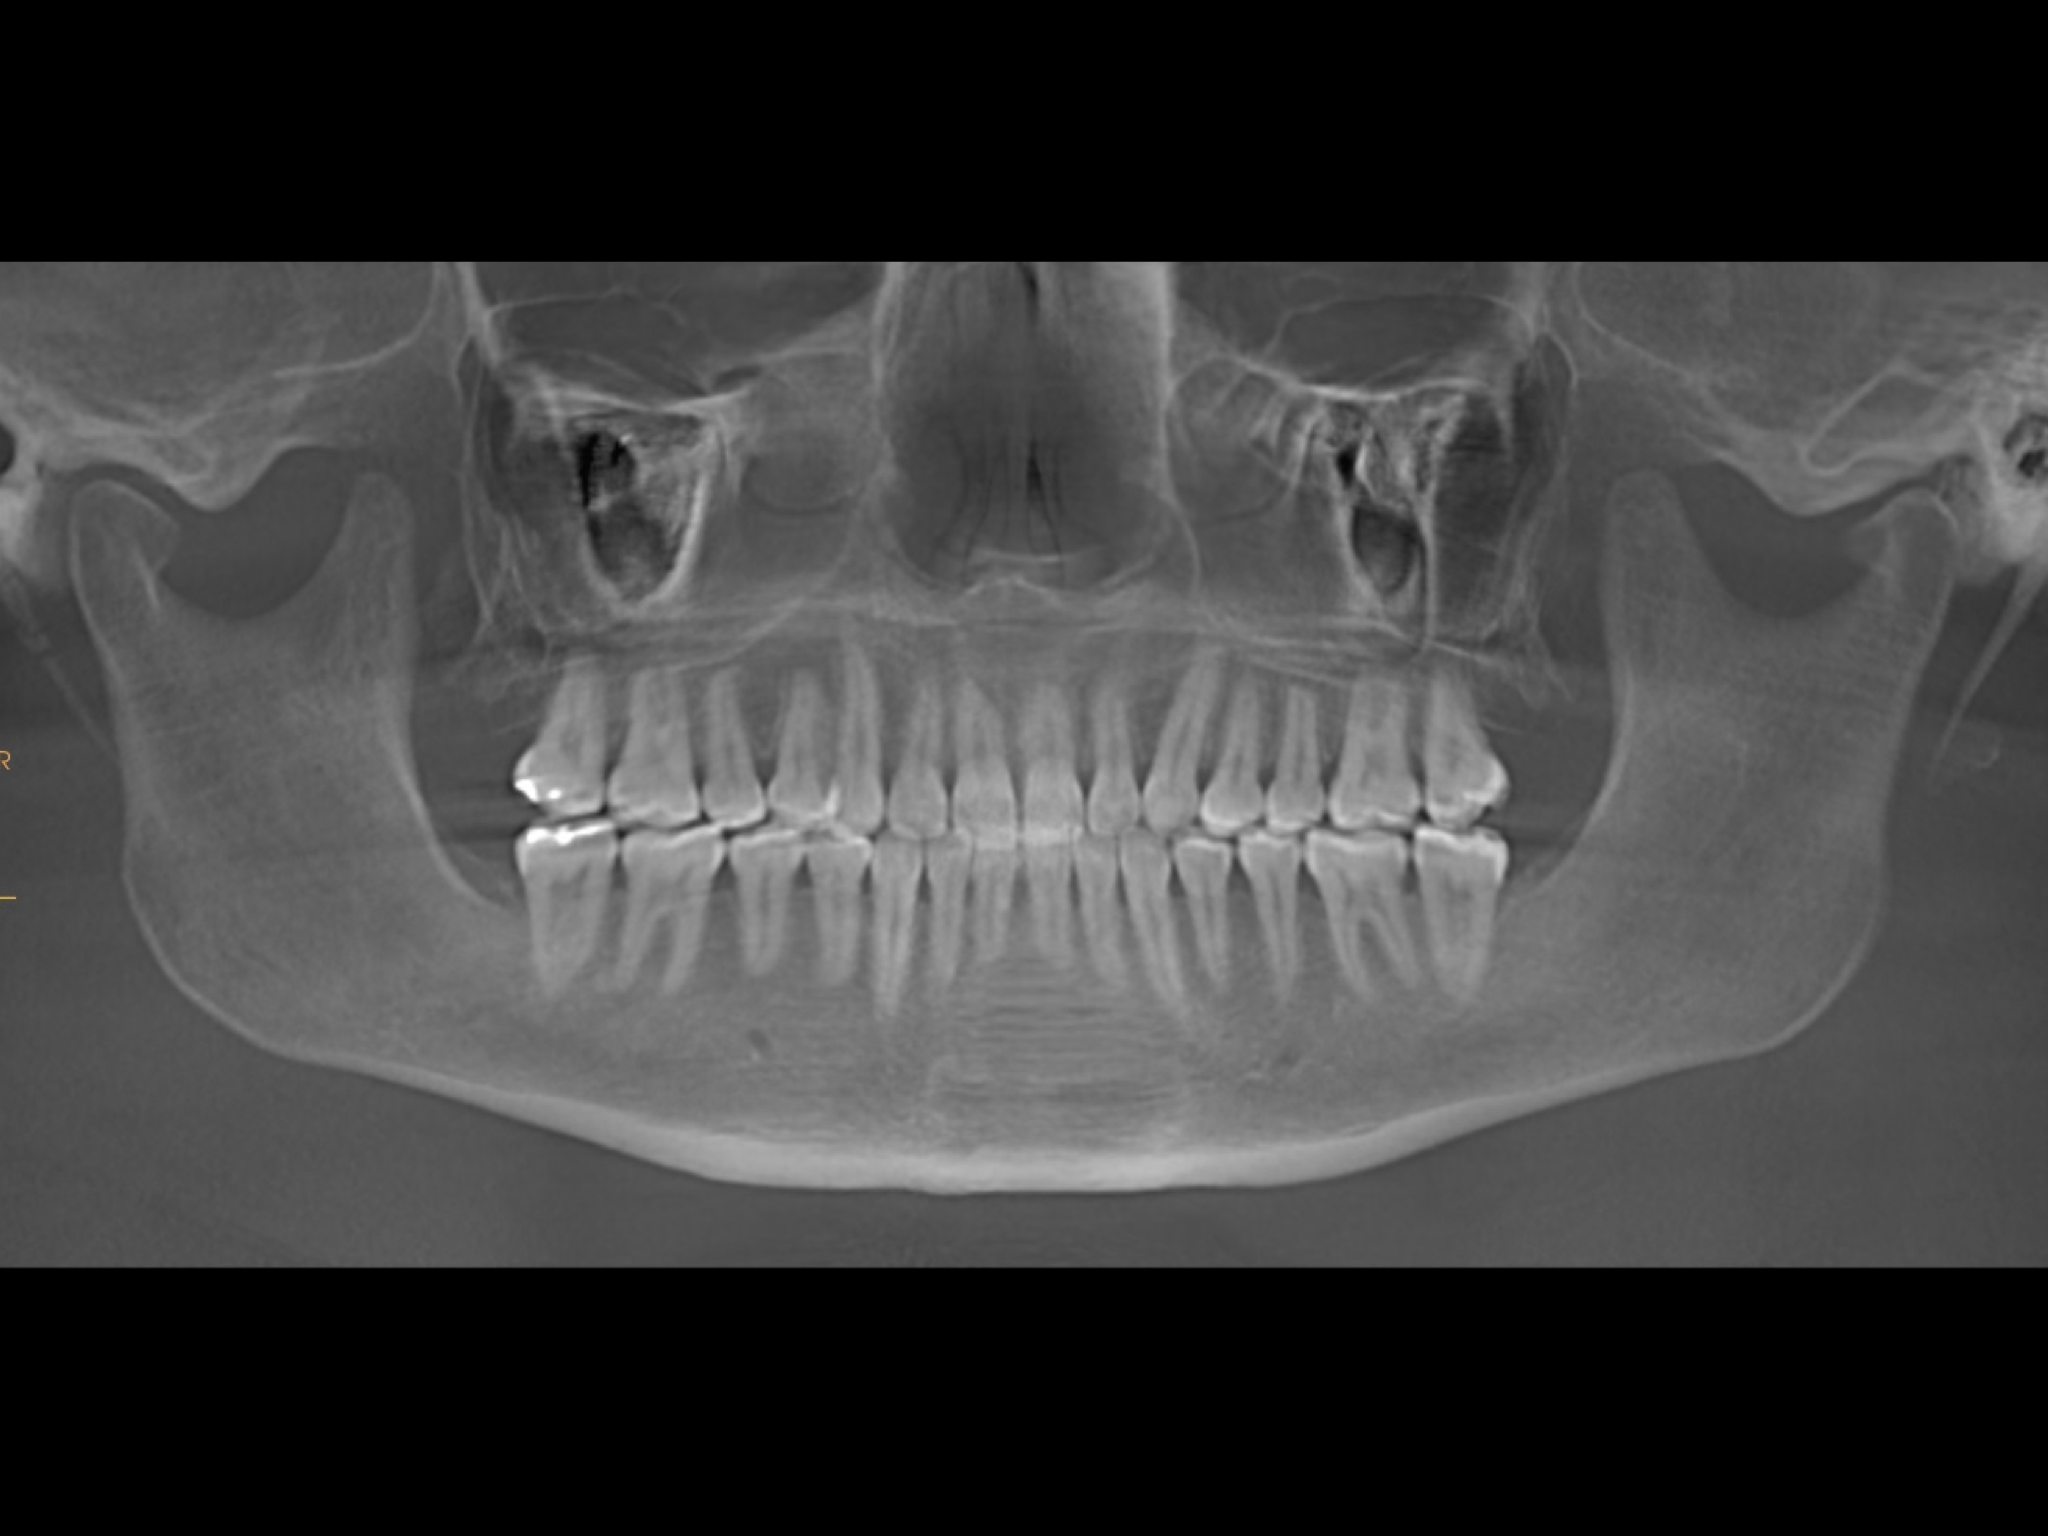

A 30-year-old female patient presented with the chief complaints of severe muscle and joint pain, open bite and tooth wear. She was treated orthodontically as a teenager with fixed appliances. Extra-orally, we observed slight mandibular asymmetry with deviation of the chin to the right, as well as lip incompetence, insufficient chin projection and a long face typical of a dolichofacial skeletal pattern (Fig. 2). Intra-orally, she had an anterior open bite, retroclined maxillary incisors, moderate crowding in both arches, an asymmetrical arch form uneven gingival margins, a mandibular midline shifted to the right, abfractions, gingival recession and wear facets (Fig. 3). The joint and muscle examination revealed pain on palpation of the masseter, temporalis, and superior right and left lateral pterygoid muscles. She also exhibited pain in the bilaminar zone and both lateral poles of the condyles. Clinically, she had early clicking during mandibular opening and closing owing to anterior displacement of the articular disc in both joints. In the dental panoramic tomogram, she was missing all four third molars, but had no other noteworthy pathology (Fig. 4). Cephalometrically, she had a dolichofacial skeletal pattern and proclination of the mandibular incisors (Fig. 5).

We performed a visual treatment objective, and our goals were to lingualise the mandibular incisors, decrease the vertical dimension through intrusion of the posterior teeth and produce anticlockwise rotation of the mandibular plane. This would improve the patient’s facial profile, lip competence and articular function. The CBCT images of the joints showed that both condyles were improperly located within the fossae (Fig. 6). The joint spaces were increased and the condyles descended. The airway area on the CBCT scan showed compression (Fig. 7). The patient was referred for a polysomnographic study to rule out compromised respiratory function.